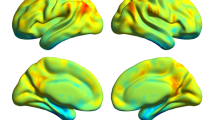

The individual correlation maps from the control group were subjected to a random-effect analysis by using a one-sample t test. The threshold was set at P < 0.05, family-wise error (FWE) corrected. The major nodes of the DMN map from the control group were then defined as the DMN seed regions (region of interest, ROI), which included the PCC/precuneus (PCUN), medial prefrontal cortex (MPFC), bilateral inferior parietal lobule (IPL), medial temporal lobe (MTL), and lateral temporal cortex (LTC). The selection of DMN seed regions was based on previous studies on DMN anatomical and functional locations [6, 16]. Characteristics of the DMN seed regions are presented in Fig. 1 and Table 2.

Figure 2 shows the common states (matrix) of FC across DMN regions, which were extracted using the K-means clustering method with cluster size = 2. The visualized network patterns of the common FC states were obtained at a threshold of 0.35 to highlight differences in connectivity pattern between the 2 states. State 1 exhibited stronger connectivity strengths across 8 DMN regions relative to state 2. In addition, we set the number of clusters to 3 and 4 when K-means clustering was performed, and similar results were observed (see Supplementary Fig. 3 and Supplementary Fig. 4).

The common states (matrix) of functional connectivity within the DMN, which was extracted using the K-means clustering method, and the visualized network pattern of the common functional connectivity states at a threshold of 0.35. The line sizes indicate functional connectivity strength in the states